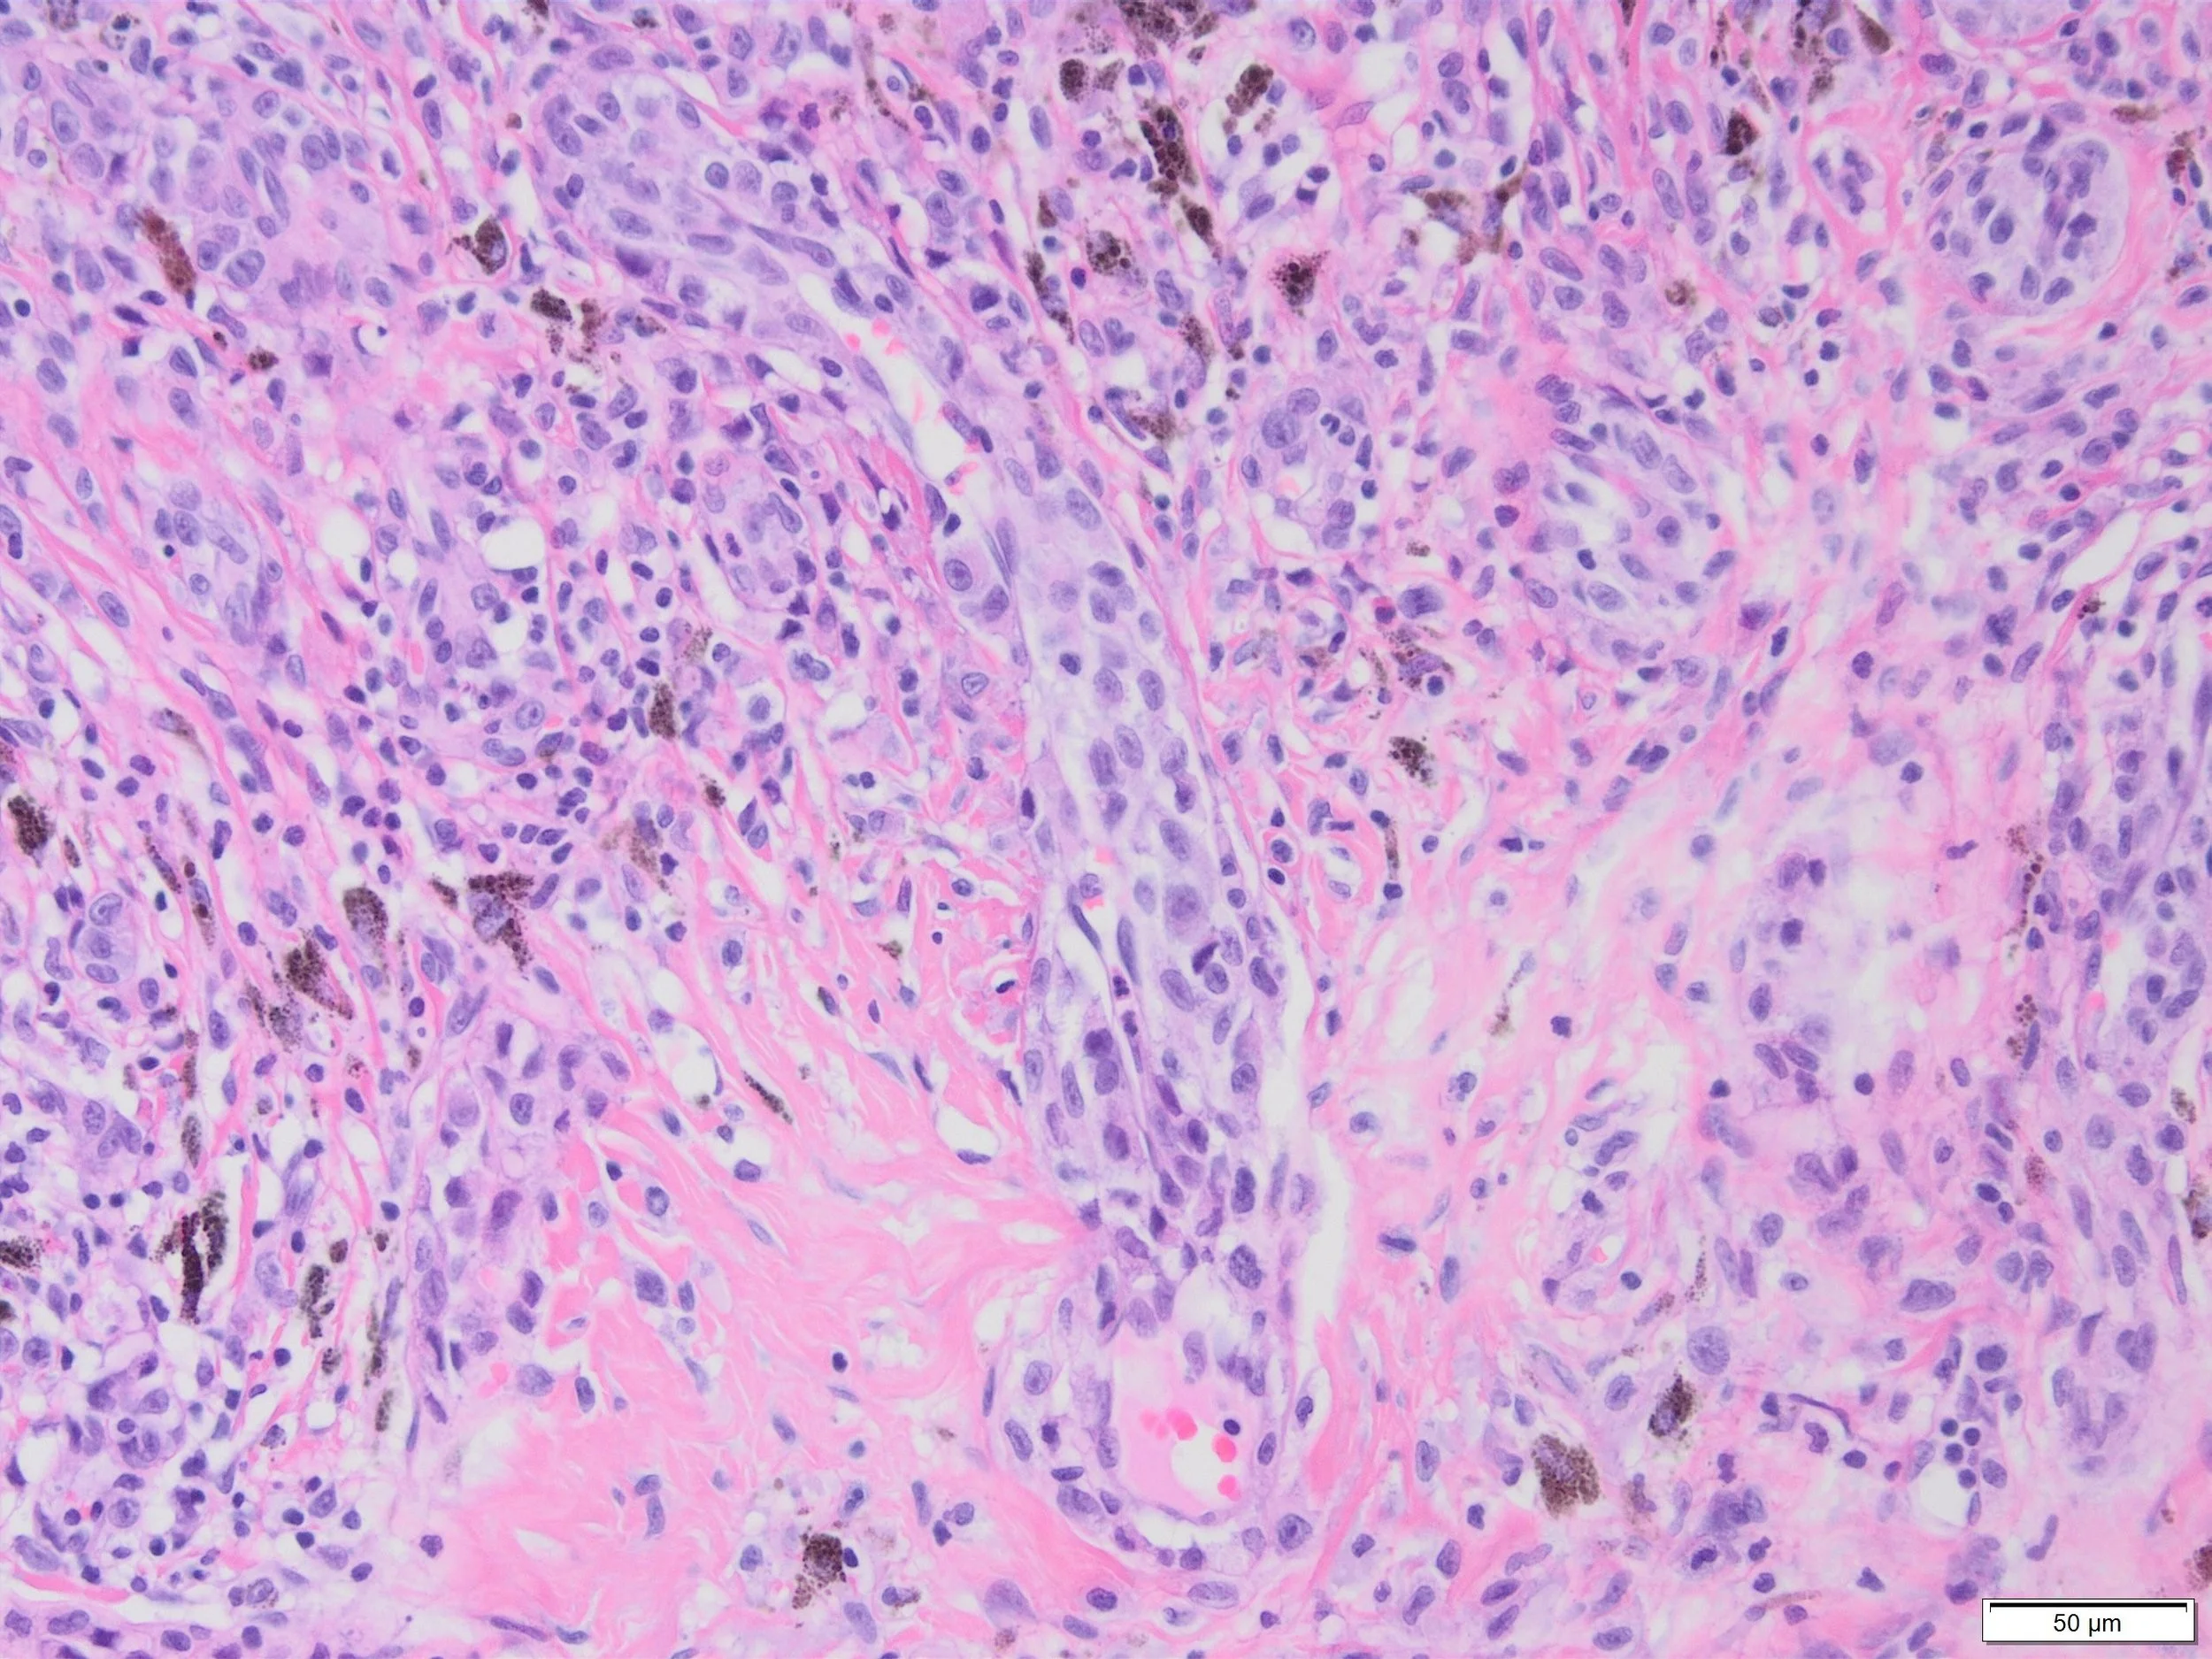

Clinical: Male 83, melanoma anterior shoulder.

The lesion is an invasive melanoma in sun-damaged skin, Breslow thickness 1.4mm, dermal mitotic rate 6/sq. mm.

What is the phenomenon demonstrated in the images from the melanoma?